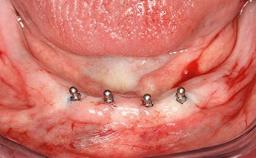

# of Implants 2

Type of Implants One-Piece

Defining Characteristics Fully edentulous lower jaw to be rehabilitated with two or more implants

Modality 2 interforaminal implants

Bone Volume Horizontally and vertically sufficient